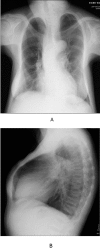

Case presentations: A 46-year-old female with chief complaints of bone pain and gait disturbance was referred to our hospital. Physical examination revealed many mobile teeth in her oral cavity, distortion of the vertebral body, and bowlegs. Laboratory tests showed hypercalcemia, hypophosphatemia, and elevated serum levels of intact parathyroid hormone. Chest CT revealed a 42-mm well-defined, enhancing mass in front of the left-sided tracheal bifurcation. Her findings were diagnosed as primary hyperparathyroidism due to an ectopic mediastinal parathyroid tumor. We performed a median sternotomy and resected the tumor. The tumor was a solid, yellowish-brown mass measuring 42×42 mm. Pathologically, the tumor consisted mainly of chief cells with some oxyphil cells; there were no necrotic areas or nuclear atypia, and few mitotic figures. We diagnosed the tumor as an ectopic mediastinal parathyroid adenoma. Eight months after the resection, her serum calcium, phosphorus, and intact PTH levels were normal.